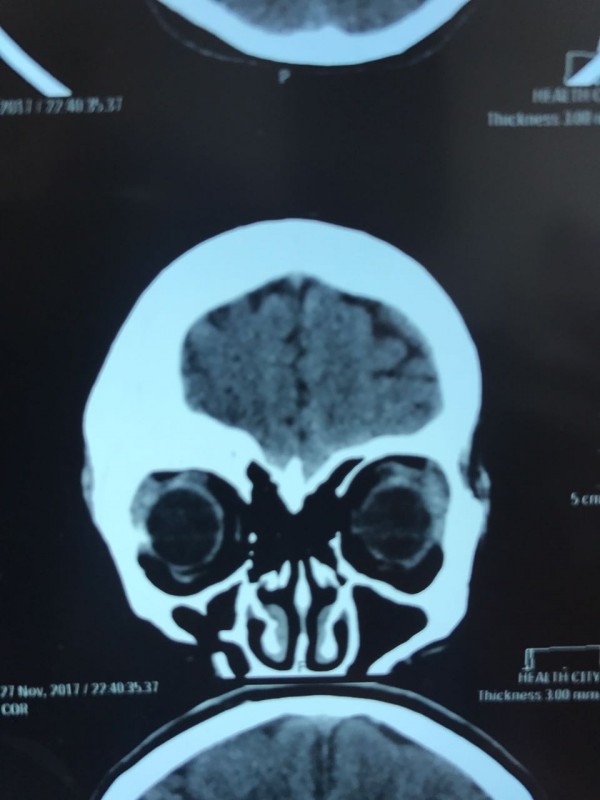

"Компьютерная томография показала, что костная опухоль поражала лобную кость и "крышу" орбиты глаза, которая, в свою очередь, сдавливала глазное яблоко. Чтобы убрать опухоль, потребовалось немало времени. Наша задача была сохранить глазное яблоко, зрительный нерв и сосуды. Если неправильно провести операцию и неправильно закрыть дефект, то в последующем это может привести к эстетической неполноте и асимметрии лица. Уникальность еще и в том, что в операции применялась 3D-стереолитография, которая делается только в Алматы", - рассказал он.

Снимок черепа. Опухоль с левой стороны. Фото предоставлено Константином Ли

Снимок сделан до операции. Фото предоставлено Константином Ли